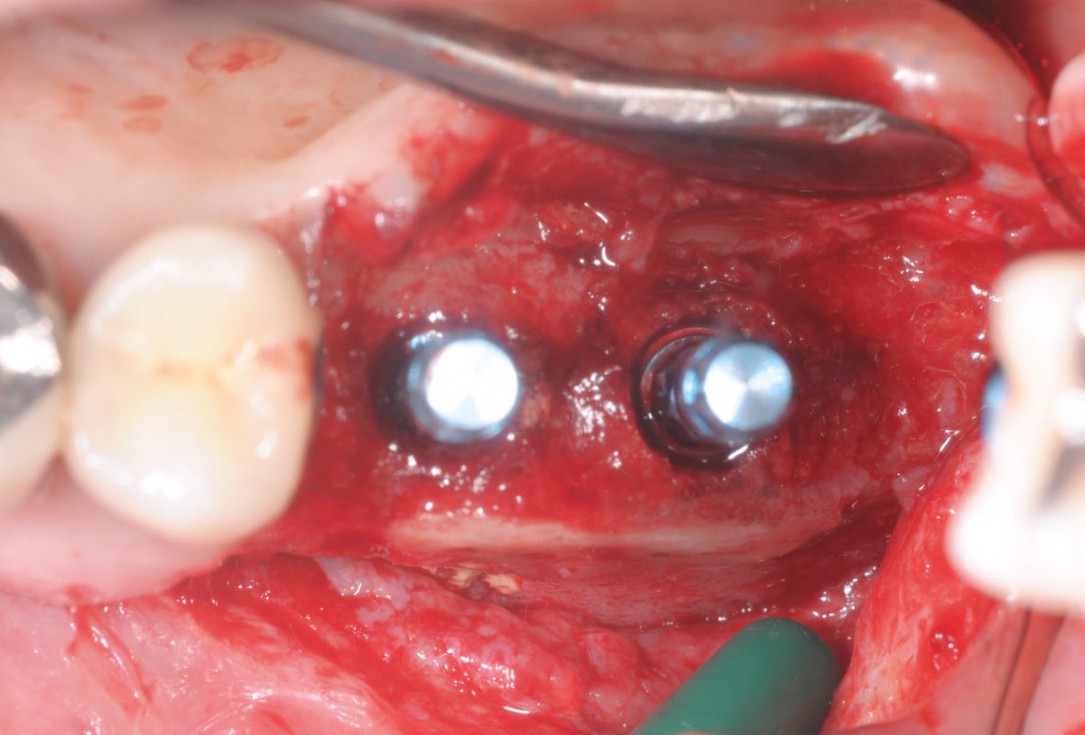

11/15 - Occlusal viewTreatment of a combined horizontal and vertical bone defect in the maxilla with maxgraft® cortico in the allogenic shell technique - Dr. R. Würdinger